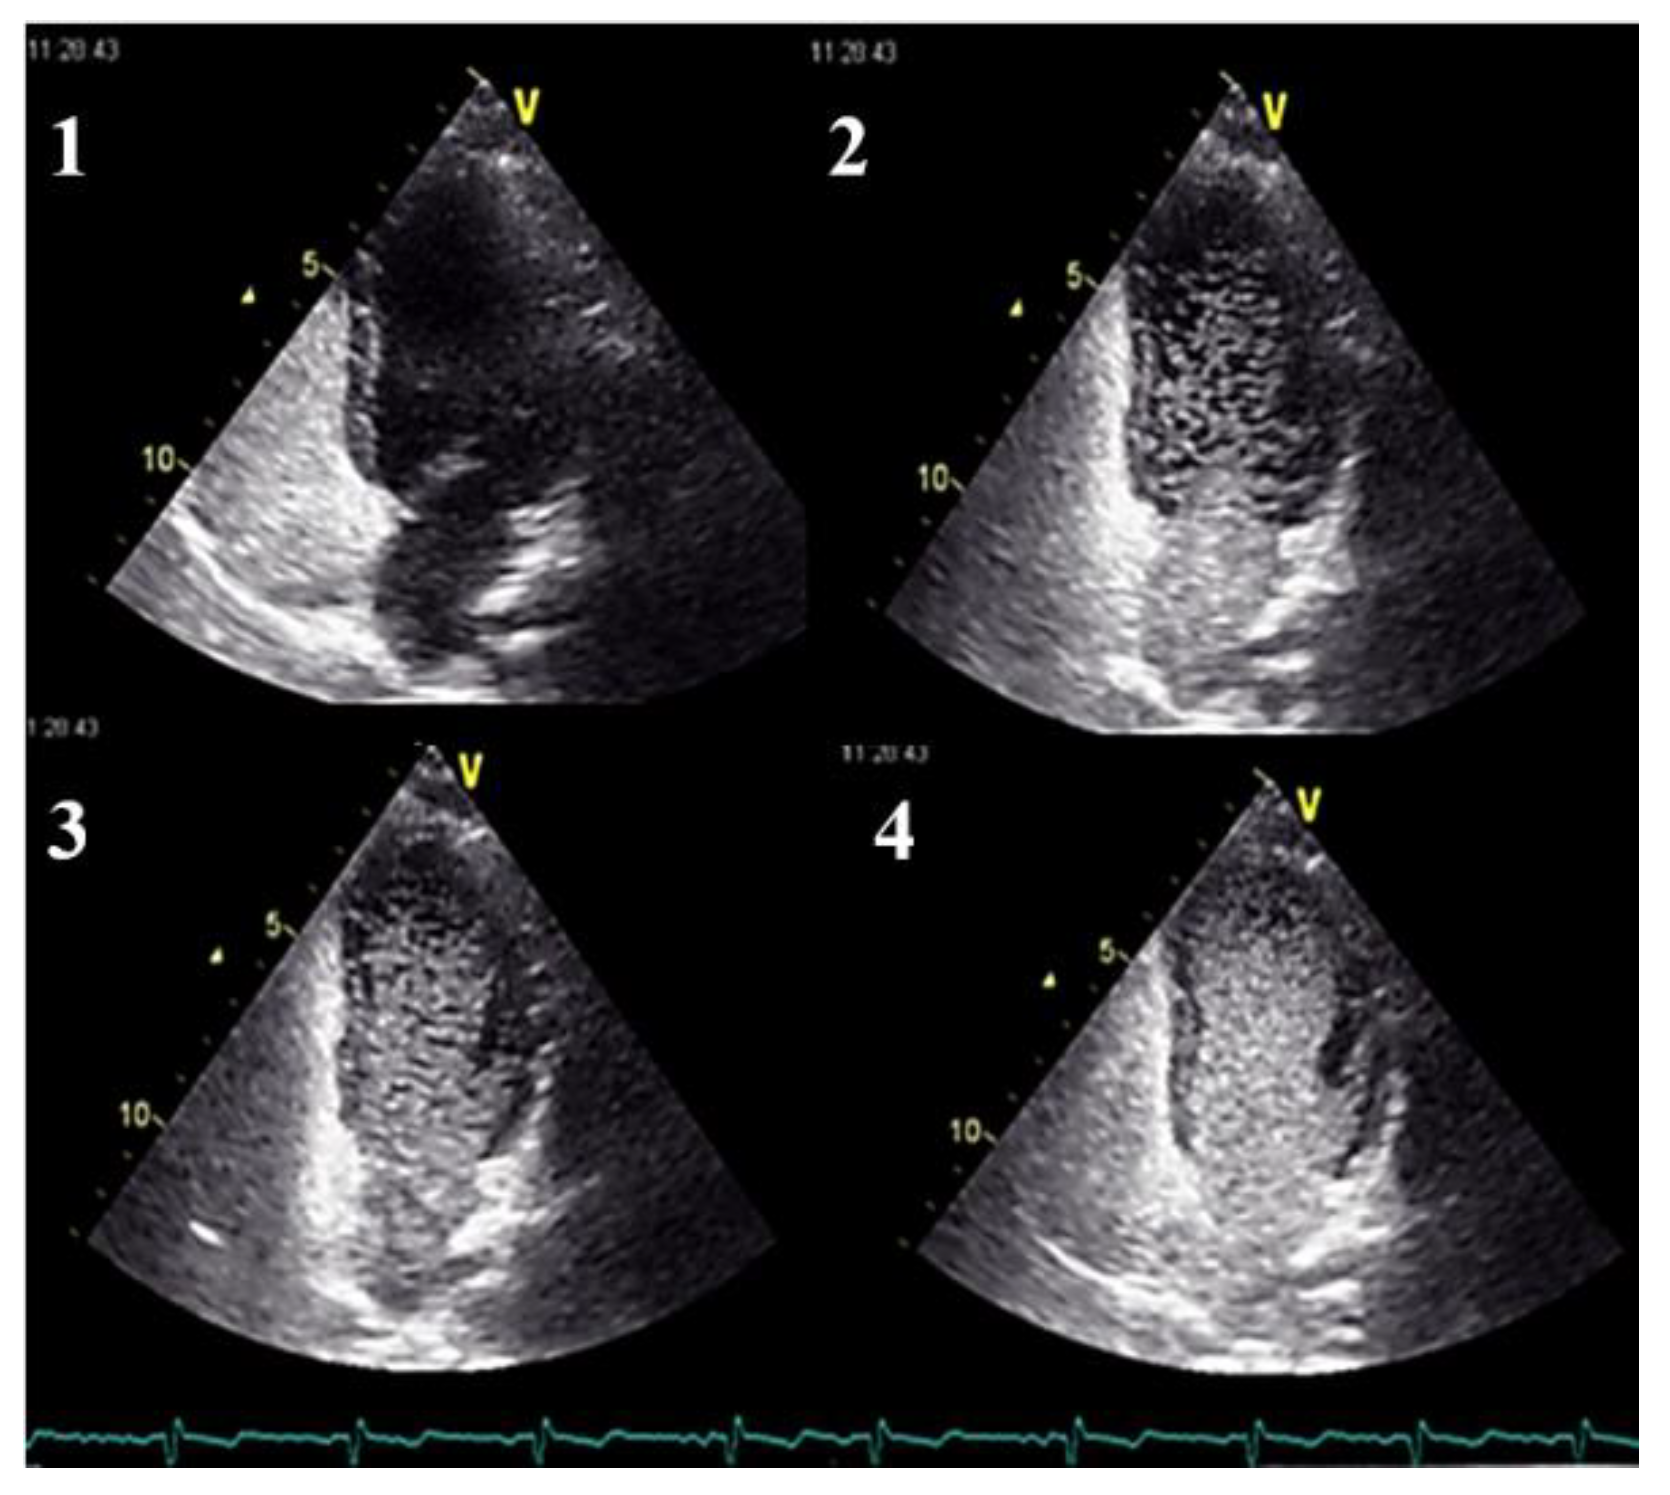

- Clinicians should use transthoracic contrast echocardiography as the initial screening test for pulmonary AVMs.

- in the absence of symptoms, pulmonary AVMs screening should be performed initially, either by an agitated saline transthoracic contrast echocardiography or by a low-dose chest CT without contrast, according to local availability and expertise. When opting for a chest CT examination, it should ideally be performed early in the second trimester.